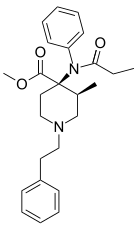

Anilidopiperidines